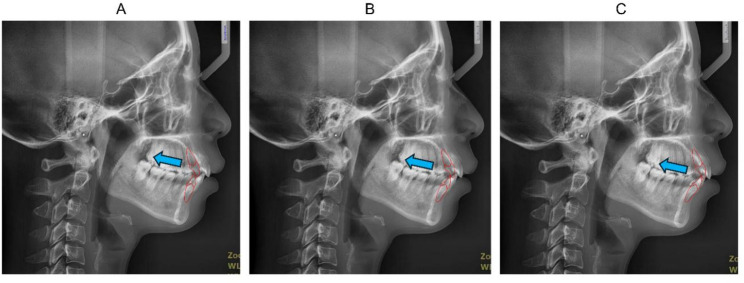

Methods: A total of 140 Chinese adult skeletal Class II cases were included, who finished orthodontic camouflage treatment with anterior retraction following premolars extraction. Post-treatment lateral cephalograms were trimmed and converted into silhouettes, rated by a panel of orthodontists. The top 30% and bottom 30% ranked cases were included as the favorable and unfavorable profile group respectively. The distances of U1 anterior to the GALL line (U1-GALL), point A vertical (U1-Av), and ANS-Pog line (U1-ANPo) were measured as IPO indicators.

Results: U1-ANPo in the favorable profile group was 4.74 ± 1.65 mm, significantly different from that in the unfavorable profile group (6.02 ± 3.61 mm). U1-GALL was -2.68 ± 2.30 mm and -1.12 ± 2.02 mm, and U1-Av was 4.49 ± 3.97 mm and 6.22 ± 4.42 mm, in the favorable and unfavorable profile group respectively, neither showing significant difference. Among three indicators, only U1-ANPo had a significant discriminatory capacity (AUC = 0.74, P = 0.007) for differentiating between the favorable and unfavorable profile group.

Conclusions: In skeletal Class II orthodontic camouflage treatment, the relatively favorable post-treatment profiles are associated with the U1 position anterior to the ANS-Pog line. U1-ANPo of around 4.7 mm could be tentatively proposed as a practical IPO reference in treatment planning for such cases.